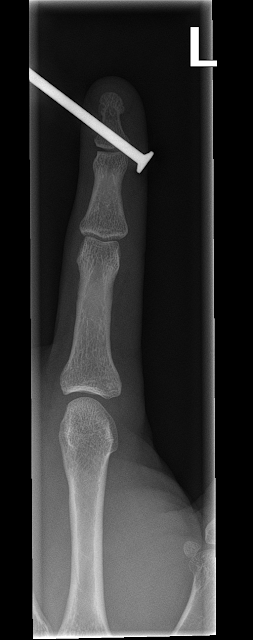

So there I was with the framing nailer just merrily nailing away, when on the hop on the recoil caused a second nail to get fired over the edge of the frame and through my finger.

I will spare the boring emerg story, and go right to the X-Rays